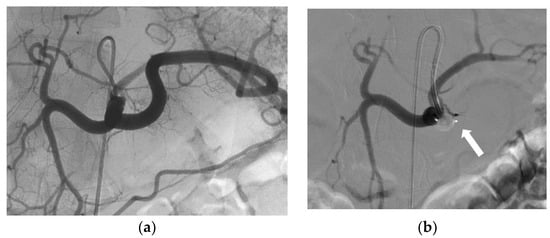

3.2. Indications and Techniques

3.3. Effectiveness